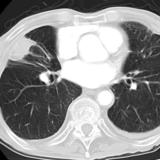

Rounded atelectasis case 1 CT